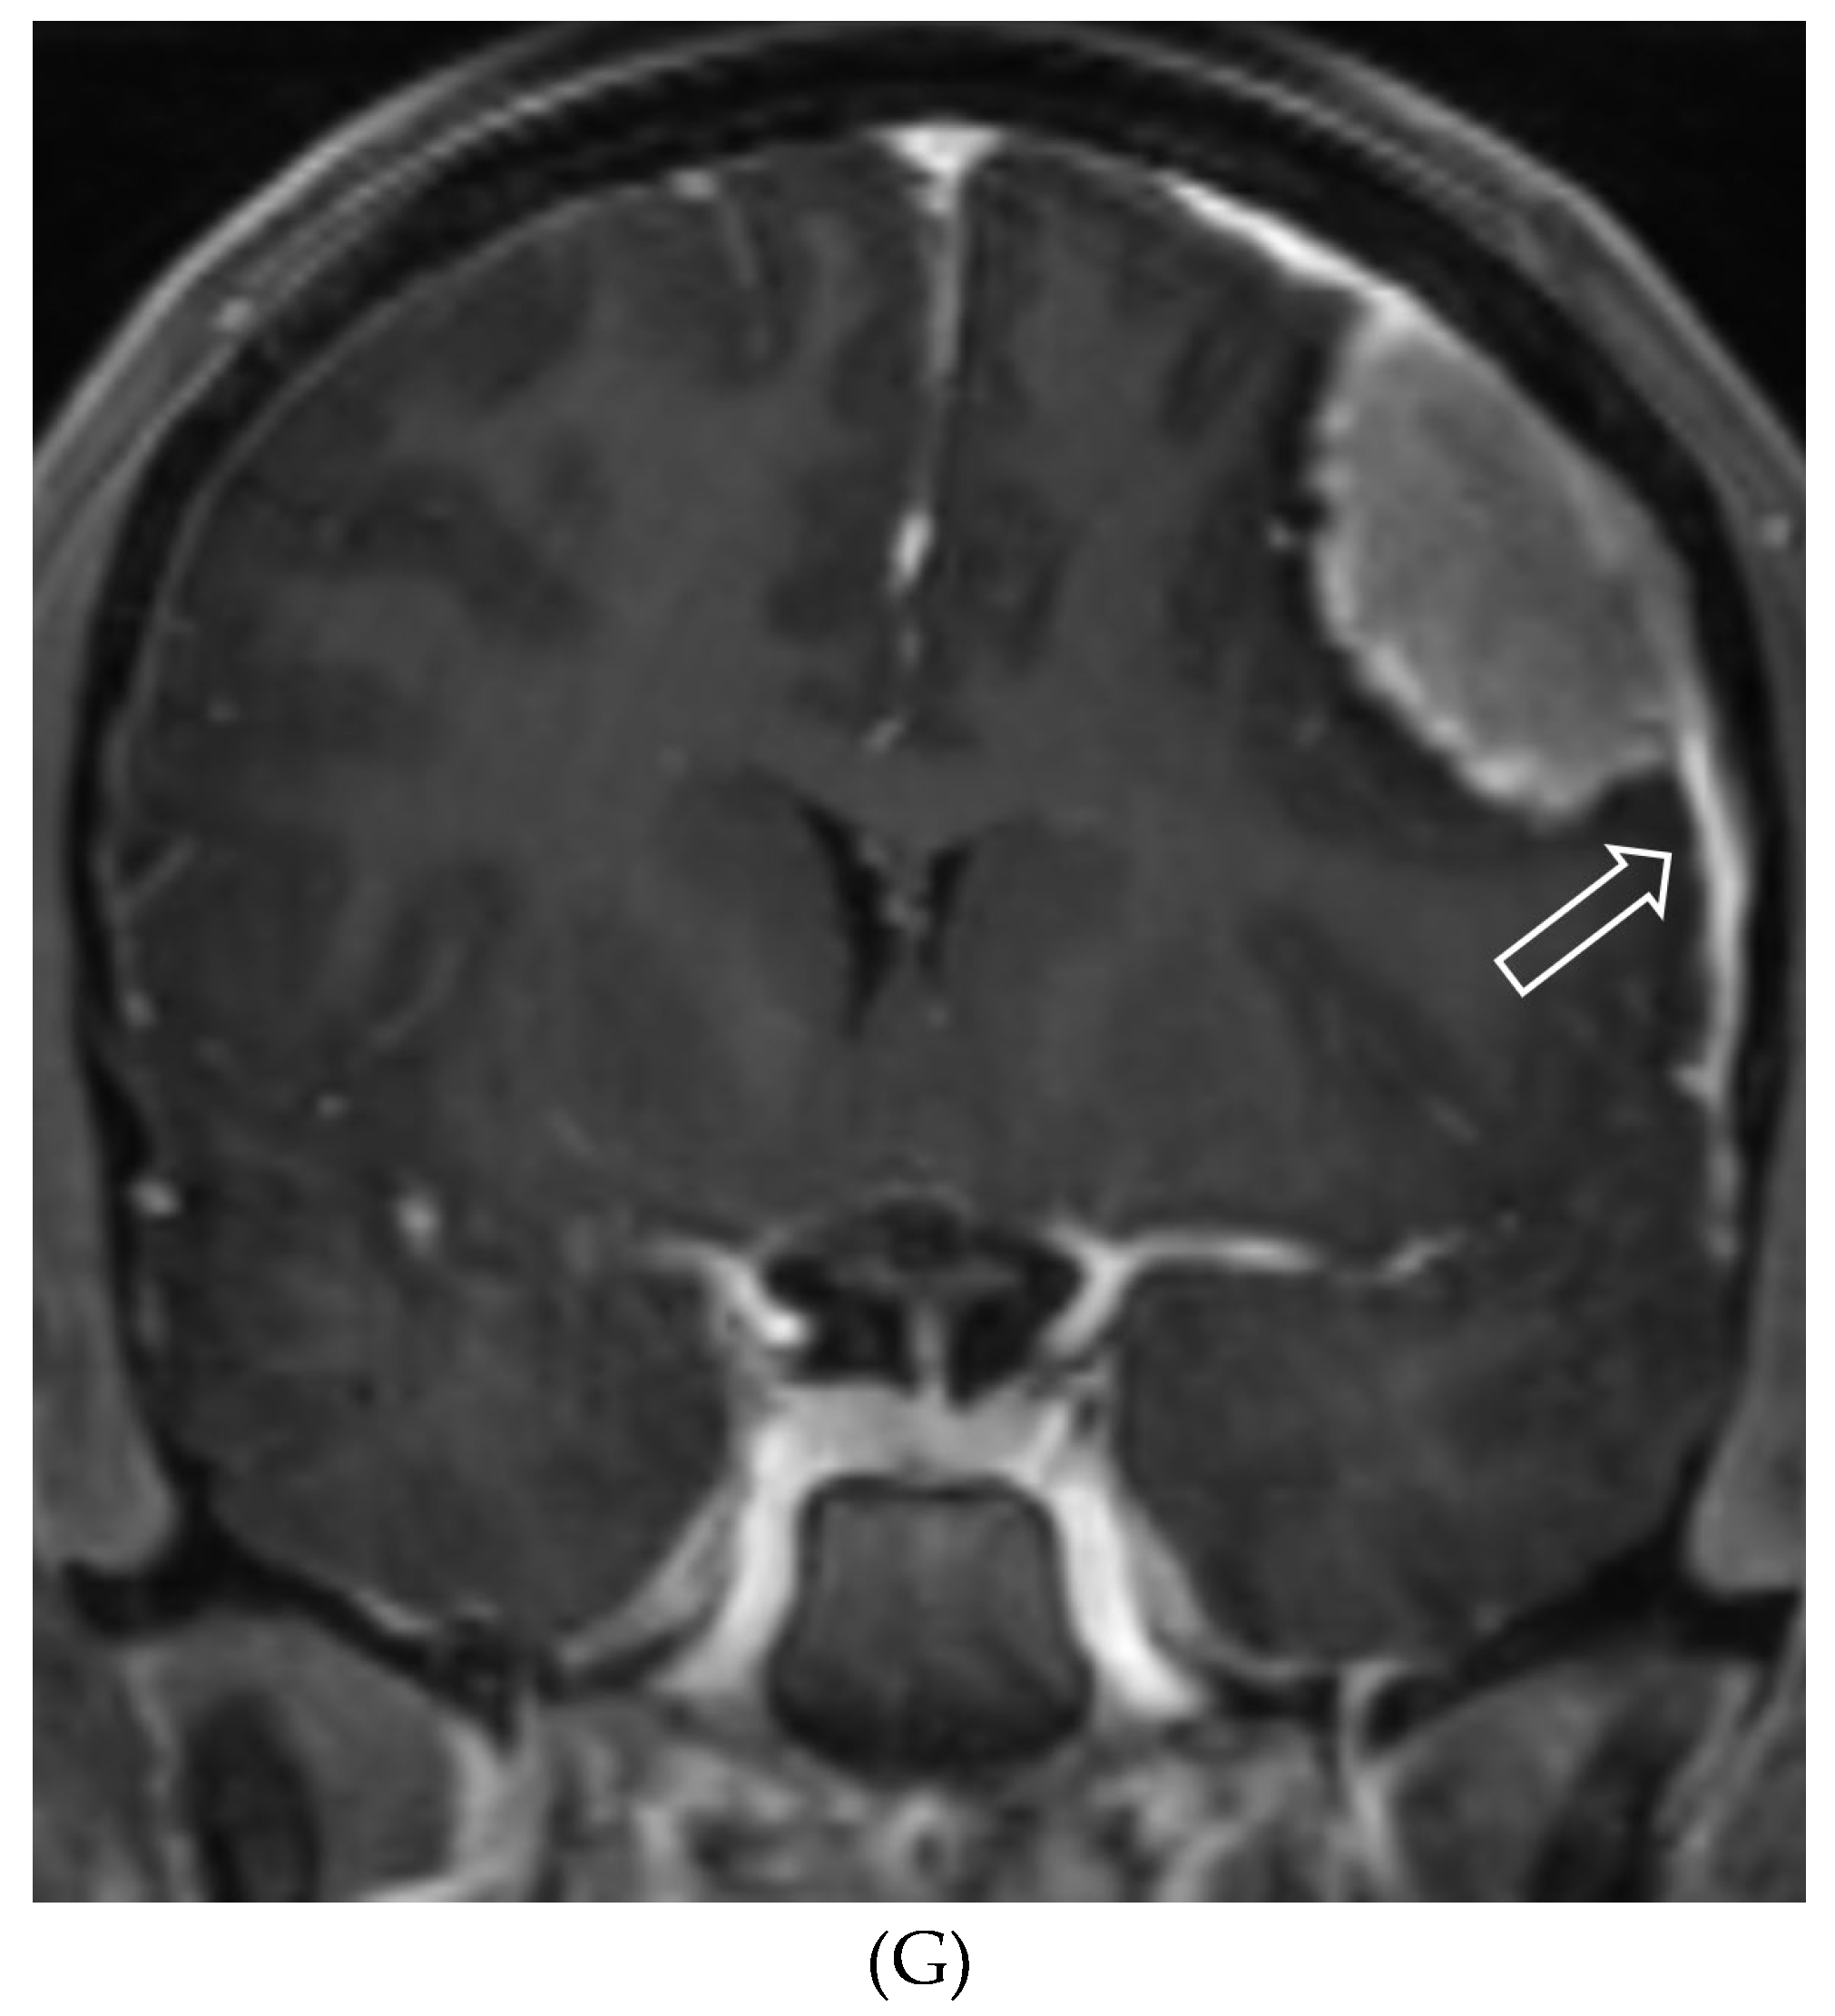

MENINGIOMA

- Menon, G., Nair, S., Sudhir, J. et al. Childhood and adolescent meningiomas: a report of 38 cases and review of literature. Acta Neurochir (Wien) 151, 239–244 (2009). [CrossRef]

- Greene S, Nair N, Ojemann JG, Ellenbogen RG, Avellino AM. Meningiomas in children. Pediatr Neurosurg. 2008;44(1):9-13. Epub 2007 Dec 14. PMID: 18097185. [CrossRef]

- Pinto PS, Huisman TA, Ahn E, Jordan LC, Burger P, Cohen KJ, Patay Z, Tekes A. Magnetic resonance imaging features of meningiomas in children and young adults: a retrospective analysis. J Neuroradiol. 2012 Oct;39(4):218-26. Epub 2011 Aug 12. PMID: 21840060. [CrossRef]

- Rochat P, Johannesen HH, Gjerris F. Long-term follow up of children with meningiomas in Denmark: 1935 to 1984. J Neurosurg. 2004 Feb;100(2 Suppl Pediatrics):179-82. PMID: 14758946. [CrossRef]

- Tenenbaum M. Extraparenchymal Lesions in Pediatric Patients. Neuroimaging Clin N Am. 2017 Feb;27(1):123-134. PMID: 27889019. [CrossRef]